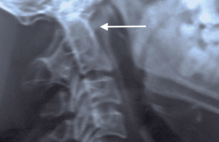

Superficial incisions were made to dissect the skin and deep fascia off completely. The superior and inferior extensor retinacula were cut to expose the tendons. The tendons of the extensor digitorum longus, tibialis anterior, extensor hallucis longus, fibularis longus, and fibularis brevis were cut at their insertions. The muscle belly of the extensor digitorum brevis and its tendons were cut to expose the underlying bones and ligaments. The length of the foot was measured using a ruler from the most posterior end of the calcaneus to the most anterior end of the second distal phalanx. Its width was measured with a ruler at the level of the metatarsal heads. The subtalar joint was cleaned with a probe to expose the CL clearly. The width and height of the cervical ligament (Figure 1-2) were measured. Its thickness was measured at the superior anterior, superior posterior, inferior anterior, inferior posterior and center points with a digital caliper (Hawk Inc., Cleveland, Ohio). The width and height of the talar neck were measured using a digital caliper (Hawk Inc., Cleveland, Ohio). The body of the talus was cut in the frontal plane and its proximal portion was removed to expose the ITCL (Figure 3). Descriptions of the ITCL were recorded for each cadaver.